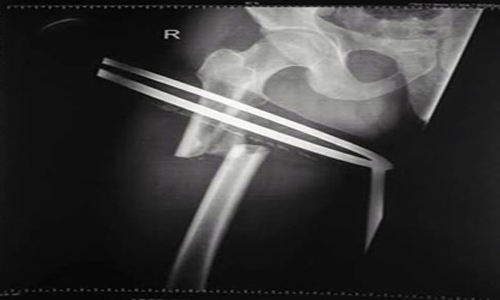

نجح مستشفى القويعية العام، في إجراء عملية تثبيت كسر لعظم الفخذ بإستخدام تقنية التثبيت بمسمار نخاعي تشابكي دون الحاجة إلى إجراء فتح جراحي واسع وذي ألم، وتعتبر هذه العملية الأولى من نوعها بالمستشفى.

وأوضح مدير العلاقات العامة والاعلام الصحي بالمستشفى سعود النداح، أن المصاب كان يعاني كسرًا مضاعفًا في الفخذ الأيمن وتقرر تثبيته بمسمار نخاعي تشابكي دون الحاجة إلى إجراء فتح جراحي واسع وبشكل عاجل، وتمكن الفريق الطبي المكون من الاستشاري الدكتور رجب علي، والاستشاري الدكتور سريان الحتاملة، واختصاصي العظام الدكتور حاتم الغنام، من إنهاء العملية بنجاح؛ مؤكدا بأن هذا النجاح يأتي بعد تأمين إدارة المستشفى للفريق الطبي كل المستلزمات الطبية التي تساعد في نجاح هذا النوع من العمليات.